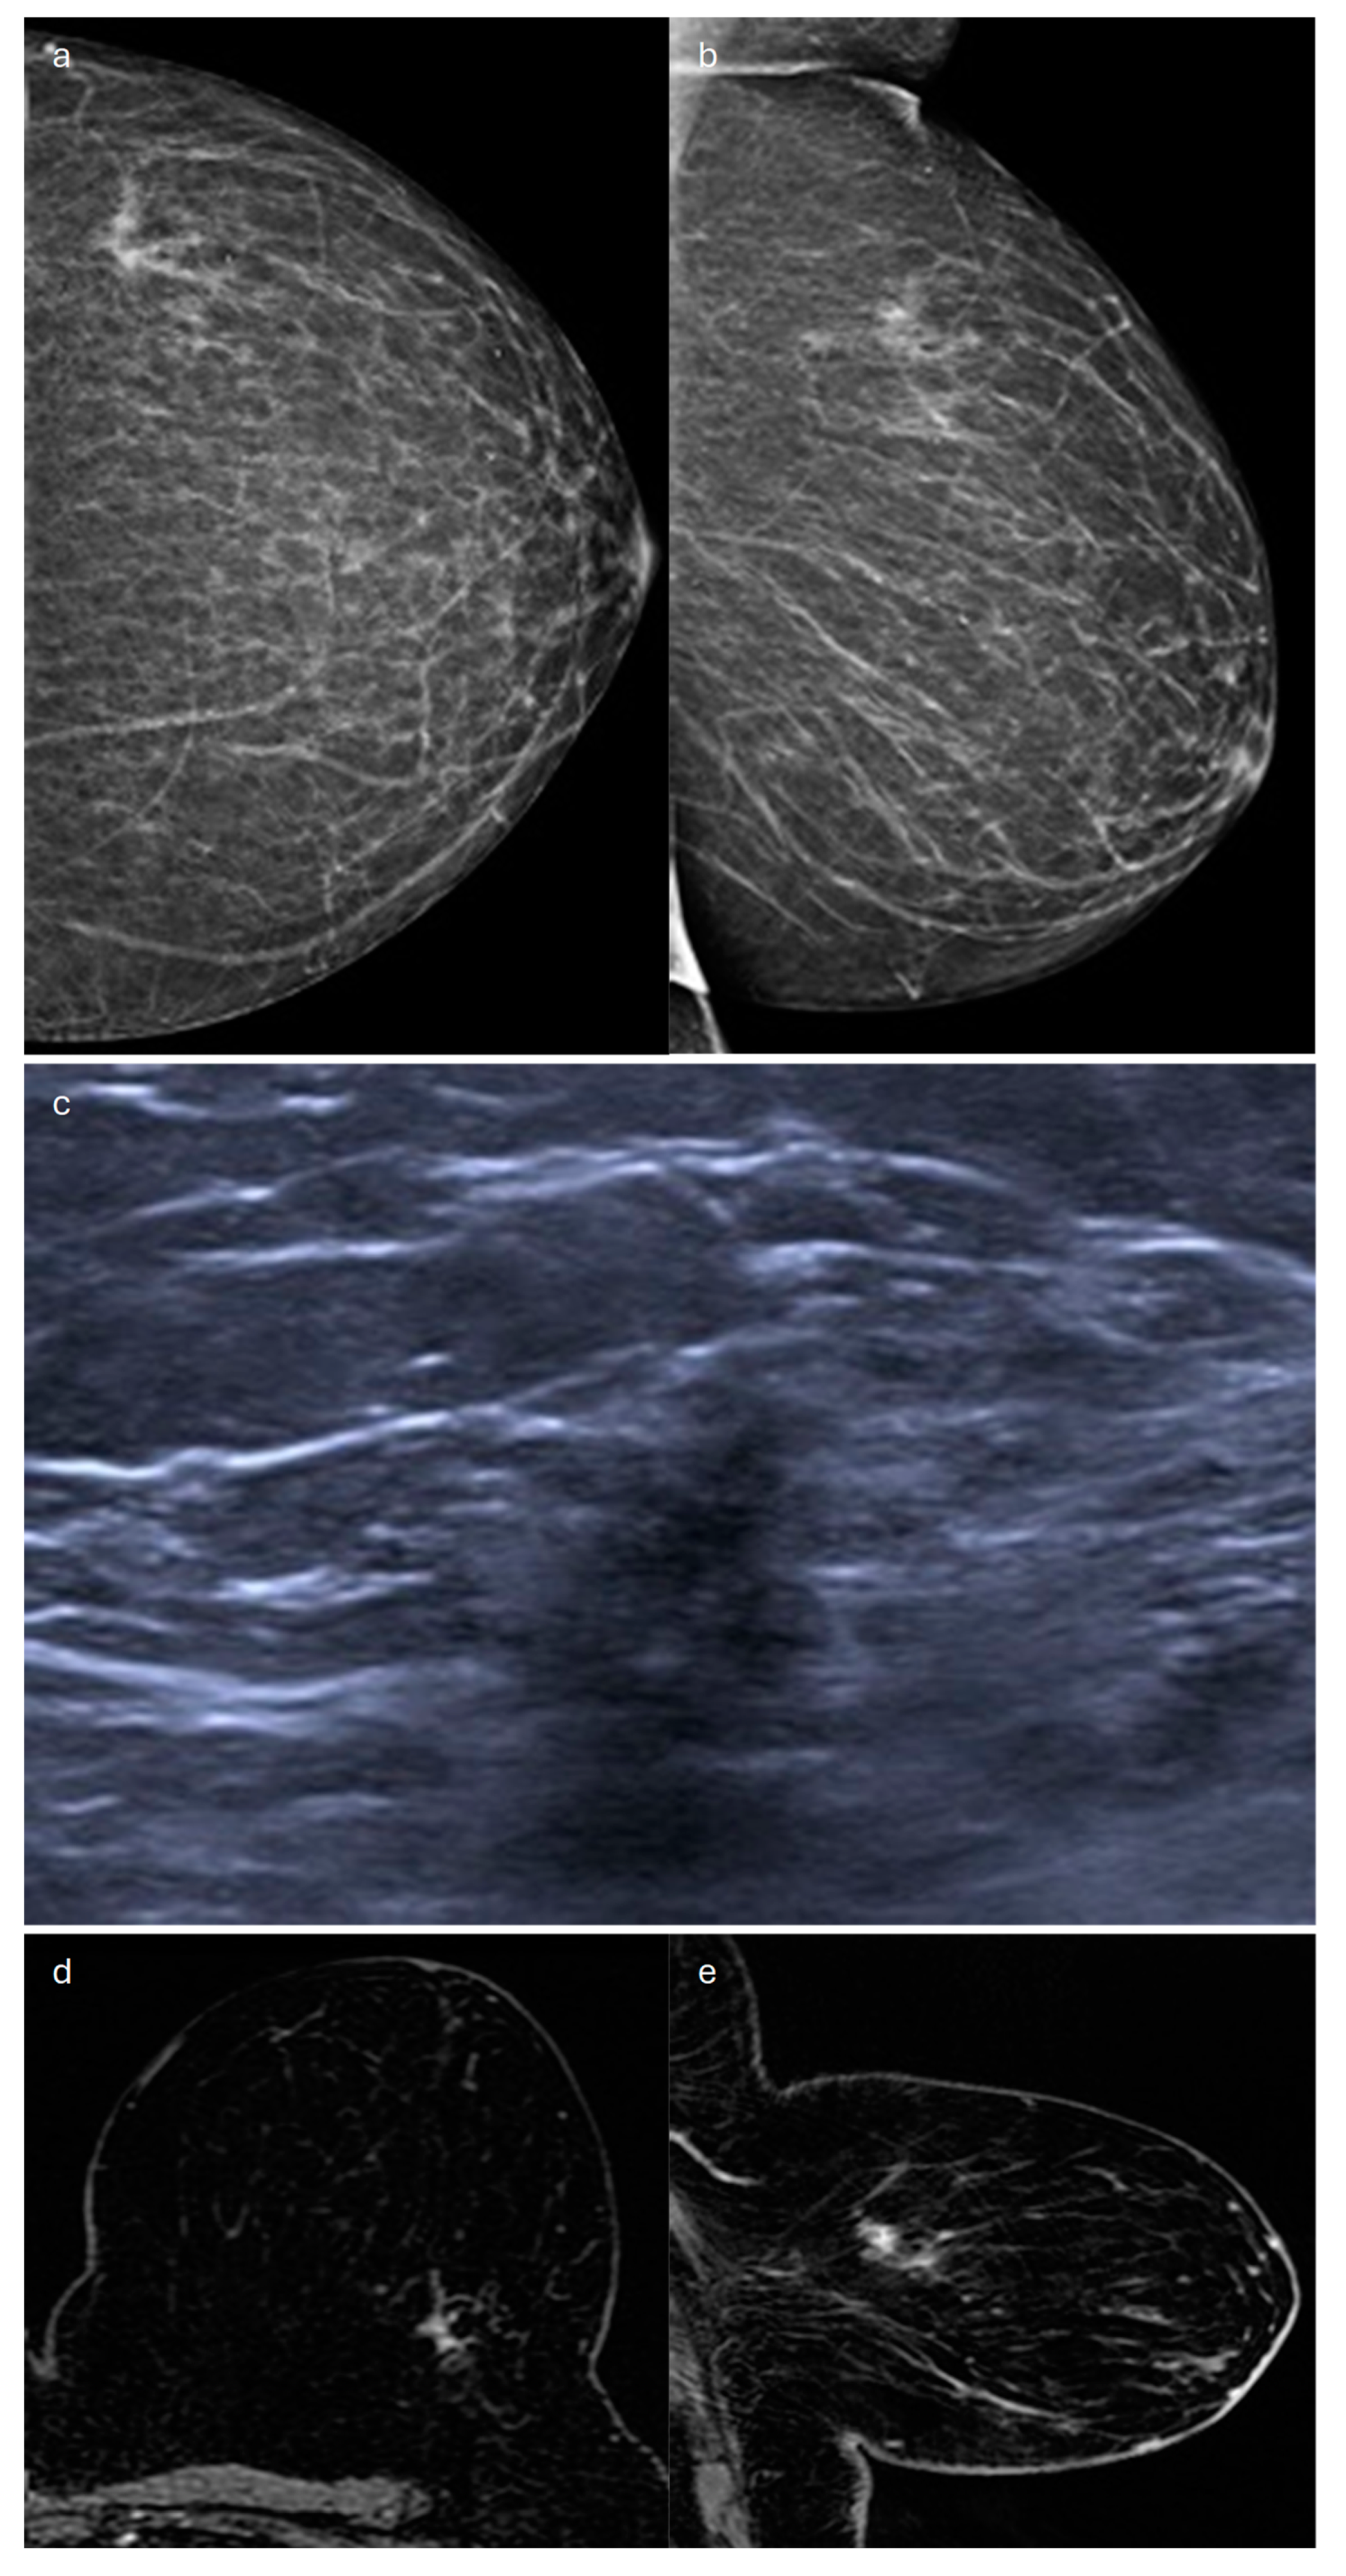

2. Lobular (Classic, Pleomorphic and Florid Types)